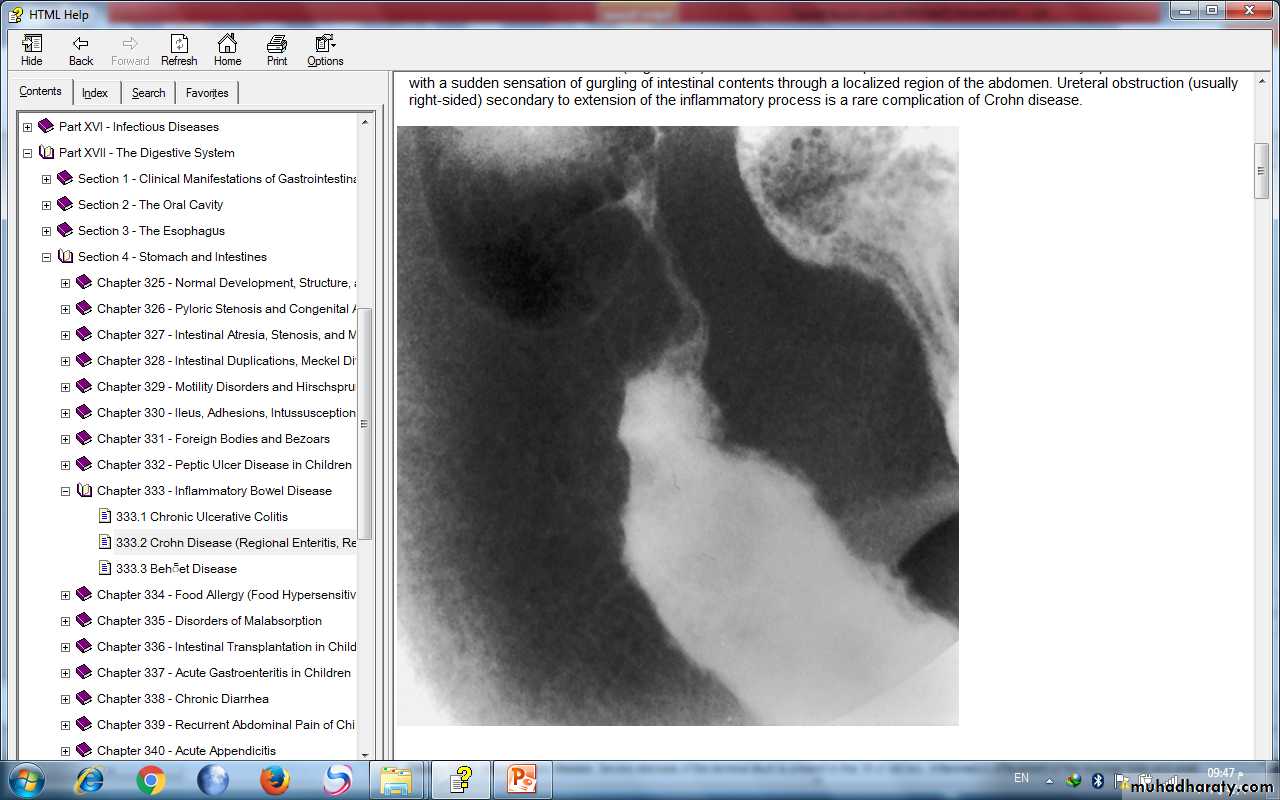

Double-contrast barium enema examination in Crohn's colitis demonstrates numerous aphthous ulcers (the tiny spots on the lining of the intestine).

Stricture, terminal ileum - colonoscopy

Severe stenosis of the terminal ileum. Inflammatory effacement of the mucosal folds and small ulcerations characterize the proximal nonstenotic segment.